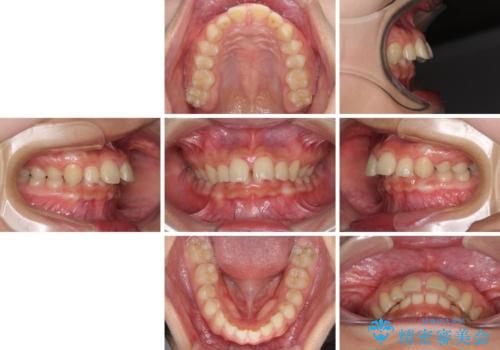

- 深い咬み合わせと上顎前歯の突出感を気にして来院された患者様です。

当院では通常、臼歯の咬合が理想的な位置に対して上顎が前方位にある場合。ワイヤー矯正または補助装置の併用したインビザライン矯正を選択しています。

今回は、できるところまででいいのでインビザライン単体で治療をしたいという希望があったため、インビザラインにて矯正治療を行うこととしました。

正面や横からの写真ではきれいに治っており、患者様は大変満足のいく仕上がりとなりましたが、深い咬み合わせの改善は不十分で、奥歯の咬み合わせも改善させることができませんでした。

インビザラインは、咬合力の強い方ですと、奥歯が歯肉内にめり込んでしまうため、前歯が強く接触してしまうことがあります。

こちらの方は、奥歯はしっかりと噛んだのですが、歯肉にめり込んでしまったことで、歯肉が腫れやすくなってしまいました。